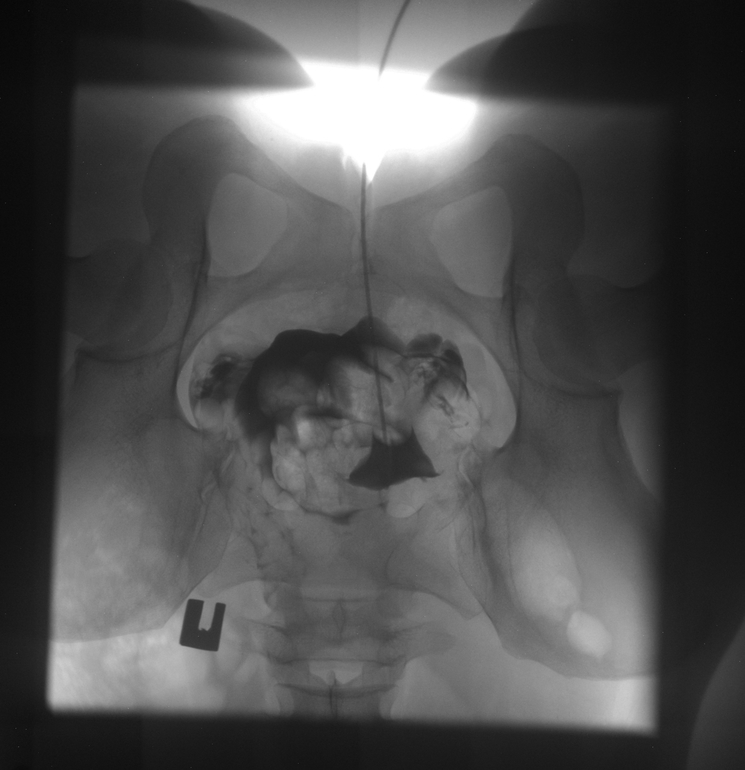

Моя ГСГ (МСГ)

ГСГ, ЭХО, МСГ, ФертилоскопияНу что, девочки, сегодня прошла я эту процедуру, такую долгожданную еще с марта.

Результат: идеально проходимые трубы, матка без патологий !

Таких идеально проходимых труб по словам гинеколога он давно не видел.

Врачи между собой переговаривались и никак не могли поверить в то что трубы настолько легко проходимы.

Матка почему то отклонена чуть влево, без видимых причин .